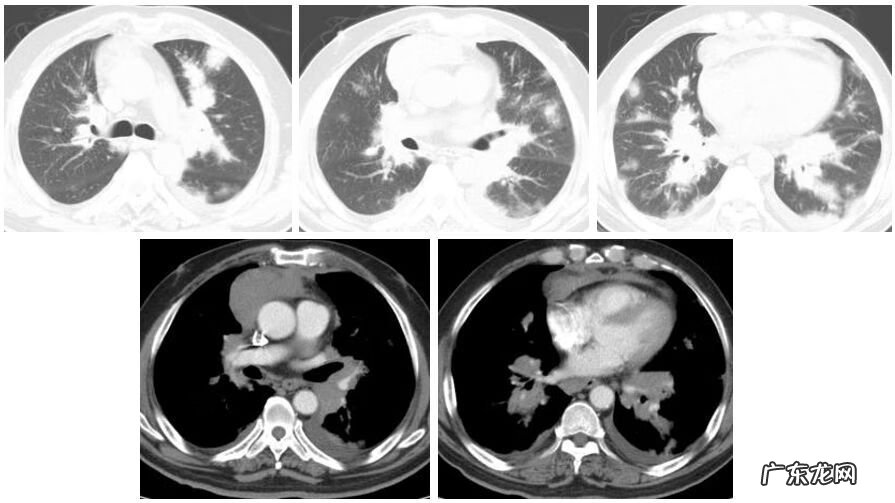

这是一位嗜酸性肉芽肿性多血管炎(EGPA)的患者,咳喘 1年余,逐渐加重,有过敏性鼻炎/鼻窦炎14年的病史 。患者出现典型的全身症状,外周血白细胞↑,嗜酸性粒细胞百分比31.2% ↑,心肌酶升高,胃肠道症状,皮疹,血沉加快,CRP增高,ANCA (-) PR3(-) MPO(-),气管粘膜活检:基底膜及间质见嗜酸性粒细胞浸润 。治疗3个月后肺内病变明显吸收(图5) 。这个病例从临床表现,就已经排除了很多疾病 。

文章插图

图5